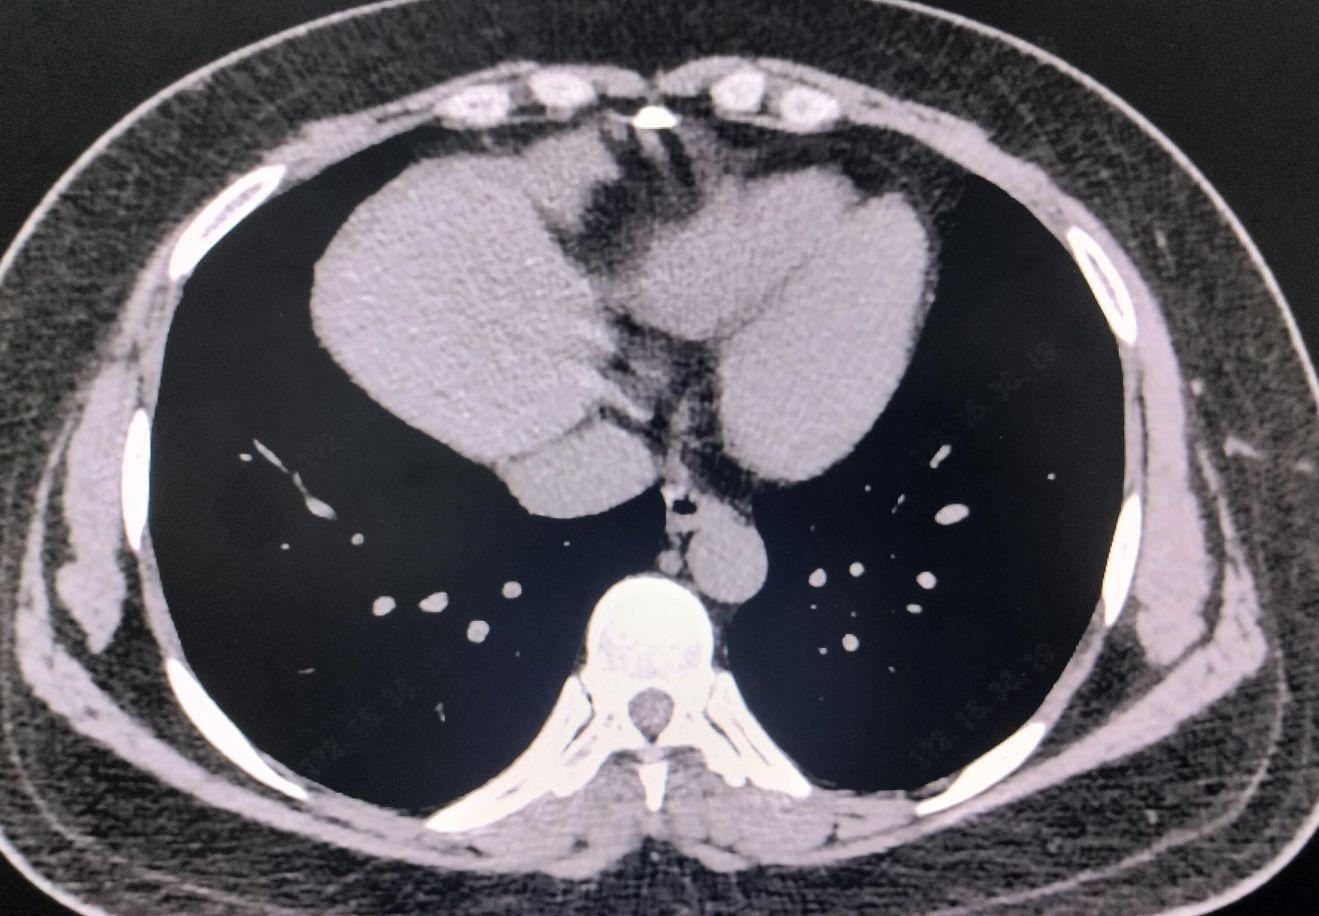

血分析:白细胞14.49*10^9/L;中性粒细胞比率88.6%,血红蛋白129g/L;C反应蛋白:12.4mg/L;凝血功能、D二聚体、肝肾功能、电解质、心肌酶谱、血脂、血糖、淀粉酶、脂肪酶、尿分析均未见明显异常;乙肝两对半:乙肝表面抗原 阳性;乙肝e抗原 阳性;乙肝核心抗体 阳性,入院4天后复查C反应蛋白:24.7mg/L;血分析:血红蛋白118g/L;复查肝肾功能、电解质、降钙素原、白介素6均未见明显异常;胸部CT:1.右肺中叶条索影,考虑陈旧灶。2.气管憩室可能。3.心包少量积液。4.所示食管中段黏膜增厚。请结合临床及内镜等检查。心电图:1、窦性心律不齐2、P-R时限短,请结合临床。电子胃镜:1、食管上段黏膜撕裂并血肿形成;2、非萎缩性胃炎伴糜烂。